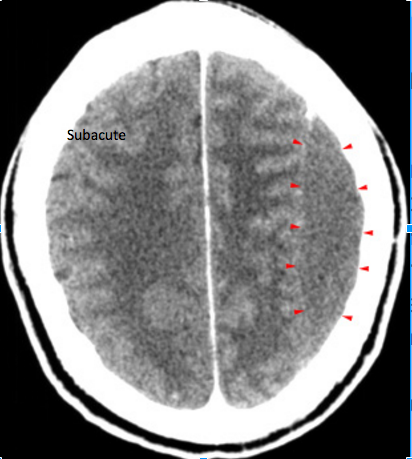

High density, crescent shaped hematoma (arrowheads)

overlying the right cerebral hemisphere. Whats important to note in this image?

Subacute subdural hematoma (arrowheads). Whats important to note about this CT?

Note the compression of

gray and white matter in the left hemisphere due to the mass effect.